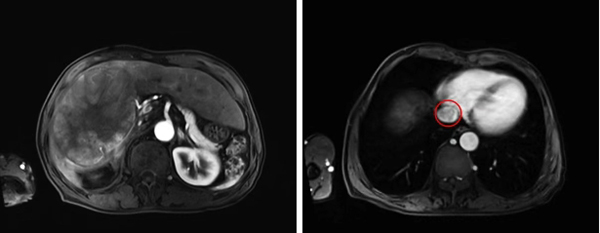

术前影像显示巨大右肝肿瘤及

下腔静脉癌栓(接近右心房水平)